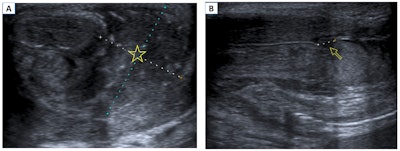

Penile fracture. B-mode ultrasound in the transverse (A) and longitudinal (B) planes. A large extratunical hematoma can be seen adjacent to the erectile bodies of the penis (star). In the longitudinal plane, a loss of continuity of the tunica albuginea (arrow) confirms its rupture.

Penile fracture is caused by a traumatic rupture of the tunica albuginea, and it occurs due to a sudden flexion of the erect penis during sexual intercourse or masturbation. Patients report hearing a cracking sound followed by sudden pain and detumescence, swelling, and deformity of the penis. It is associated with urethral injury in 10% to 20% of cases, and the treatment is always surgical, according to Telleria and colleagues. Ultrasound is the imaging test of choice to confirm the diagnosis.

Ultrasound findings include loss of continuity of the hyperechoic line of the tunica albuginea, presence of hematoma adjacent to the area of rupture, and indirect signs of urethral injury, such as air inside the corpora cavernosa. If ultrasound is inconclusive, retrograde urethrography should be performed.